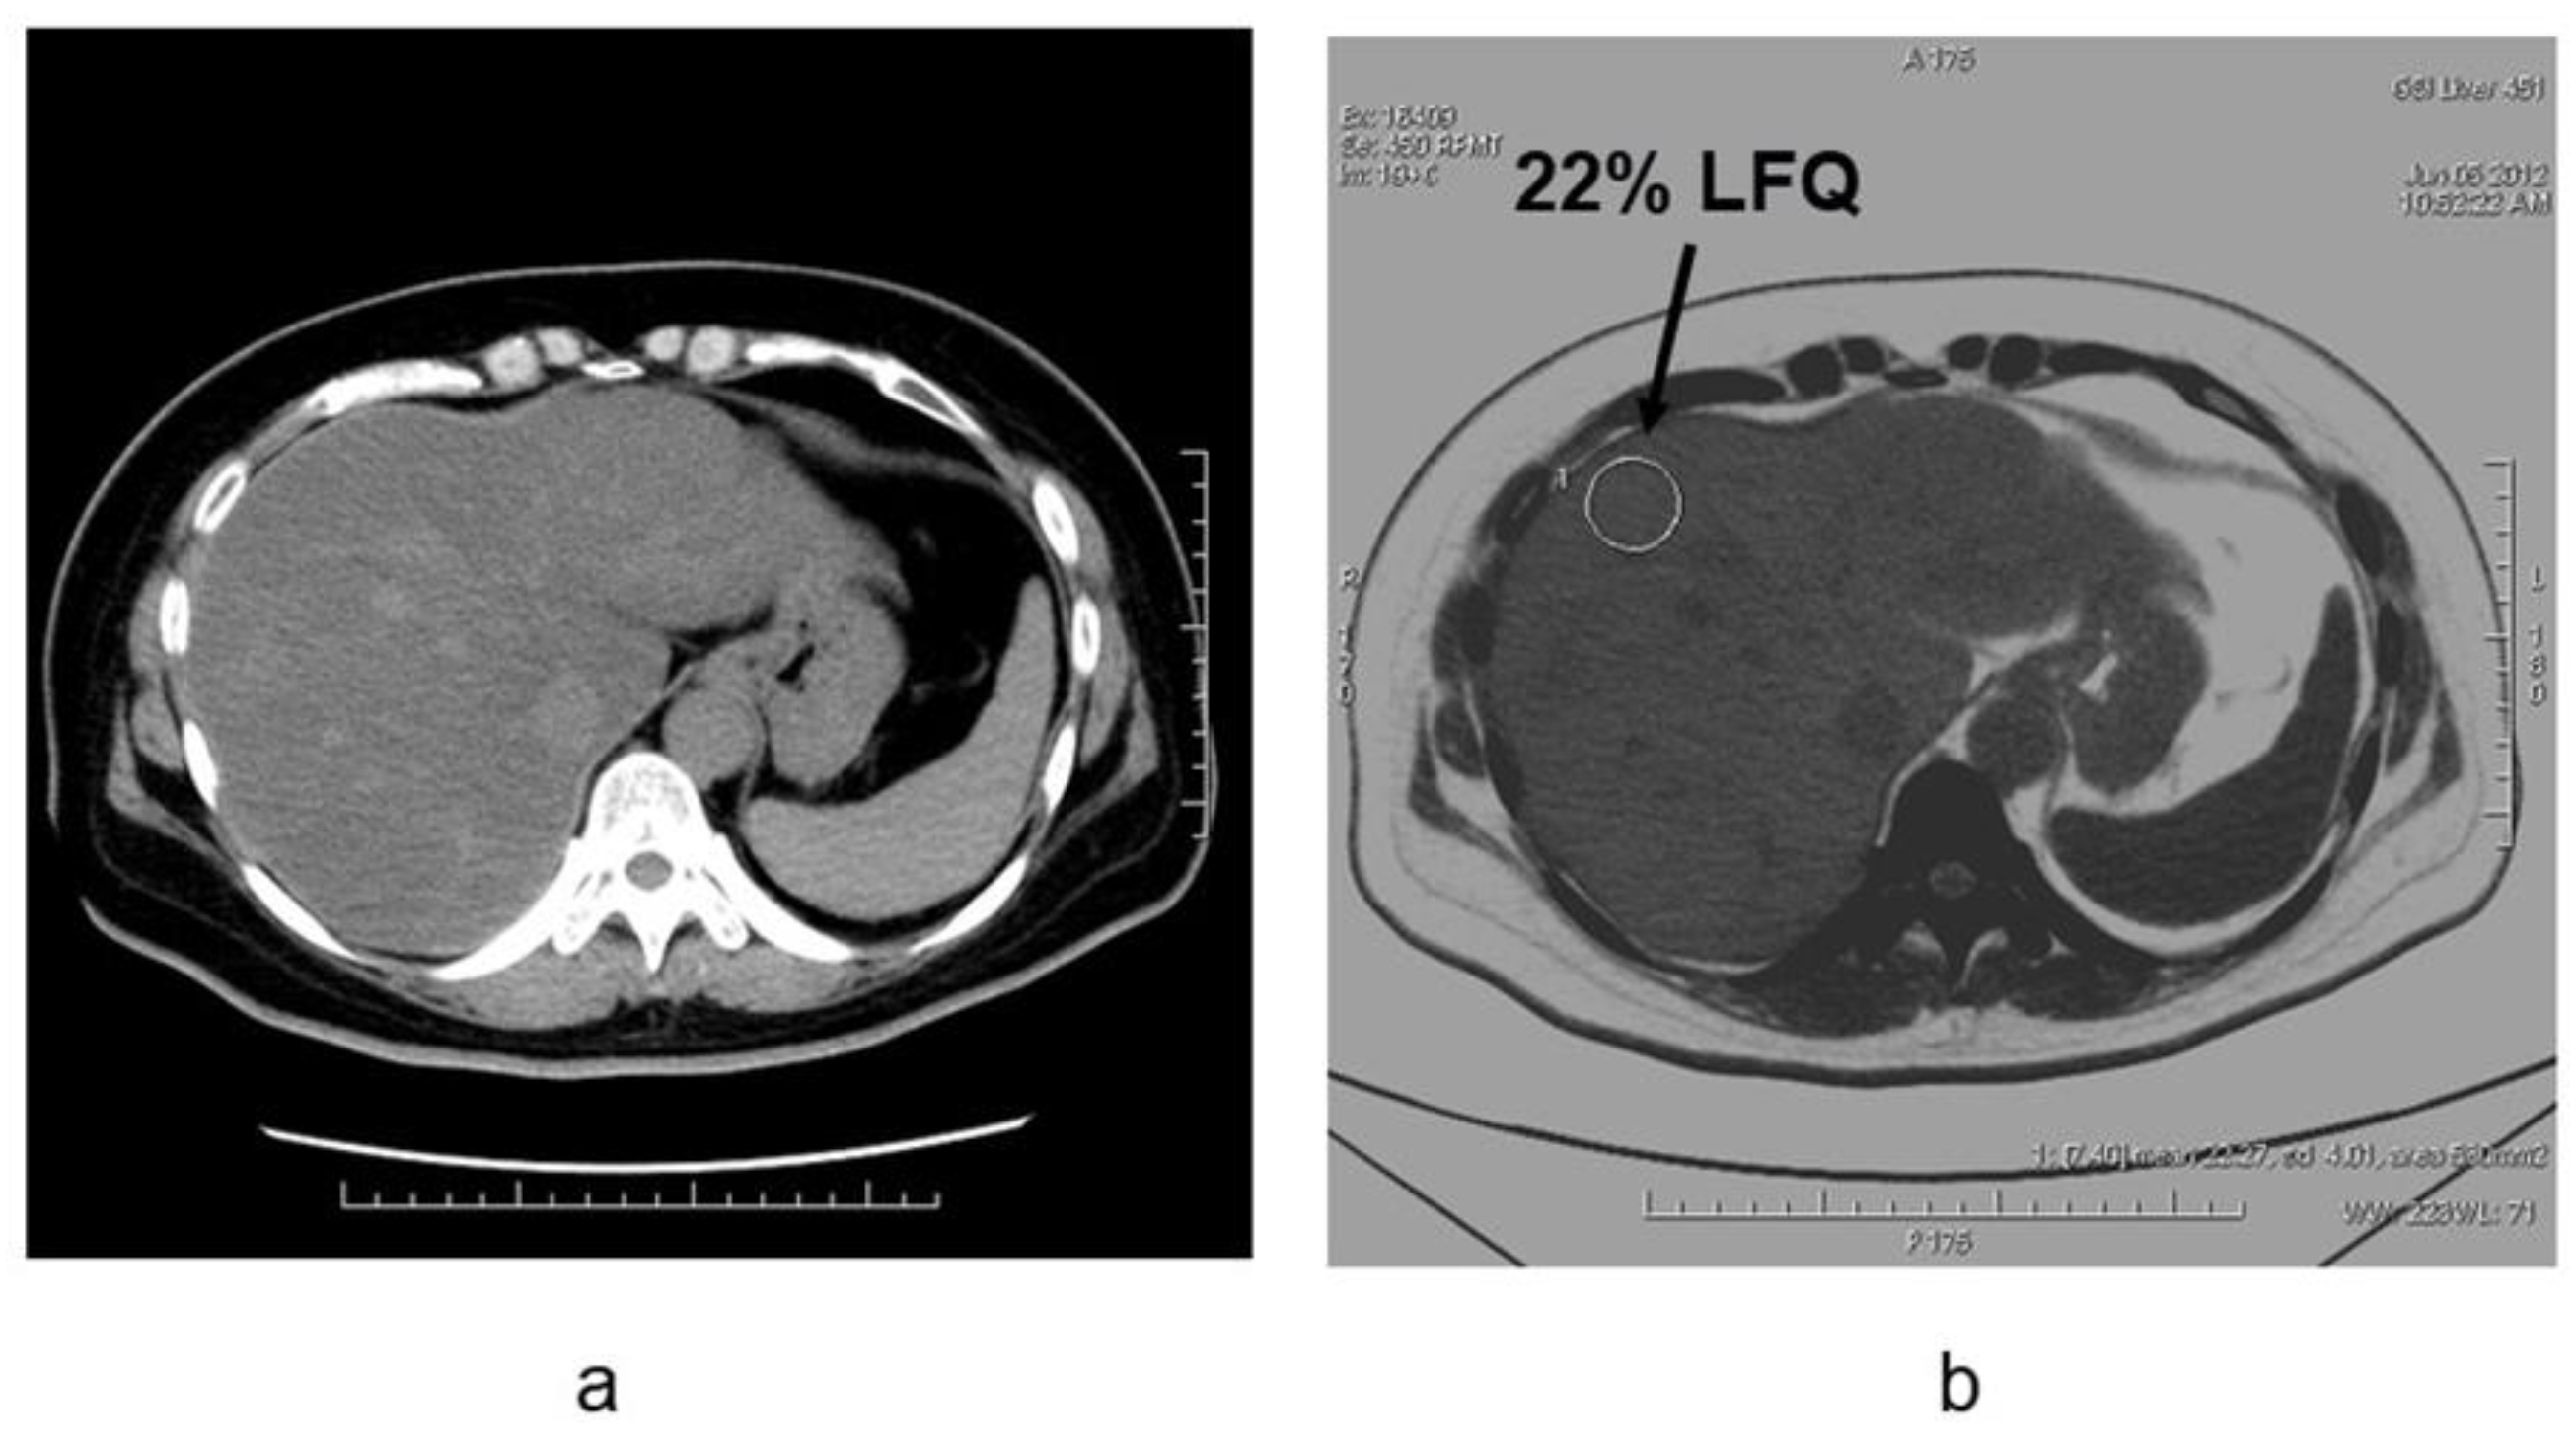

4. Evaluation of Hepatic Steatosis Using DECT

- Hyodo, T.; Yada, N.; Hori, M.; Maenishi, O.; Lamb, P.; Sasaki, K.; Onoda, M.; Kudo, M.; Mochizuki, T.; Murakami, T. Multimaterial Decomposition Algorithm for the Quantification of Liver Fat Content by Using Fast-Kilovolt-Peak Switching Dual-Energy CT: Clinical Evaluation. Radiology 2017, 283, 108–118. [Google Scholar] [CrossRef]

- Hyodo, T.; Hori, M.; Lamb, P.; Sasaki, K.; Wakayama, T.; Chiba, Y.; Mochizuki, T.; Murakami, T. Multimaterial Decomposition Algorithm for the Quantification of Liver Fat Content by Using Fast-Kilovolt-Peak Switching Dual-Energy CT: Experimental Validation. Radiology 2017, 282, 381–389. [Google Scholar] [CrossRef]